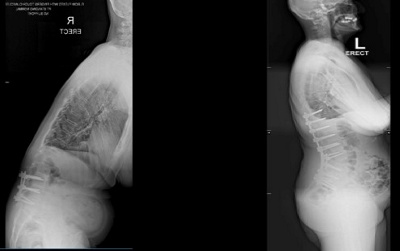

As with anything else in nature, the growth and development of the spine may not always go according to plan. Early onset scoliosis is sometimes caused by congenital anomalies, syndromic etiologies or neuro-muscular causes, such as cerebral palsy or muscular dystrophy, and results in young children seeing the side-to-side deformity of the spine developing before the age of 10.

If left unchecked this potentially devastating condition results in severe spine and chest wall deformity through growth. This in turn may result in lungs that are underdeveloped in terms of functionality. In the long term, thoracic insufficiency syndrome may occur – a condition with cardiorespiratory compromise and a diminished life expectancy.

According to Dr Davis, there are a number of surgical options to consider if conservative modalities fail, or are not deemed appropriate. Each of these carry their own difficulties and potential problems. “The universal theme is one of guided or controlled growth, where we allow the spinal column to lengthen through normal growth. The curvature of the spine is controlled, limiting the progression in deformity until we have seen adequate growth to allow near normal (functional) respiratory capacity. At this point a definitive fusion procedure can be done, allowing for a final and permanent solution.” To facilitate this controlled growth for young patients, innovative solutions are required.”

A magnetic growing rod consists of single or dual titanium spinal rods that contain a magnetically drivable lengthening mechanism. The outcomes of these growing rods are favourable in certain aspects compared to the traditional growing rod technique, where open surgical lengthening had to be performed every six months. Implant associated complication (breakage) rates are similar: however infection risk and number of surgical interventions and anaesthesia events are significantly less. This helps with the treatment of a specific patient group with a condition that is very difficult to treat, often with high complication rates, irrespective of the technique used to treat them.